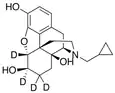

The pharmacodynamic response to an opioid depends upon the receptor to which it binds, its affinity for that receptor, and whether the opioid is an agonist or an antagonist. For example, the supraspinal analgesic properties of the opioid agonist morphine are mediated by activation of the μ1 receptor; respiratory depression and physical dependence by the μ2 receptor; and sedation and spinal analgesia by the κ receptor. Each group of opioid receptors elicits a distinct set of neurological responses, with the receptor subtypes (such as μ1 and μ2 for example) providing even more [measurably] specific responses. Unique to each opioid is its distinct binding affinity to the various classes of opioid receptors (e.g. the μ, κ, and δ opioid receptors are activated at different magnitudes according to the specific receptor binding affinities of the opioid). For example, the opiate alkaloid morphine exhibits high-affinity binding to the μ-opioid receptor, while ketazocine exhibits high affinity to ĸ receptors. It is this combinatorial mechanism that allows for such a wide class of opioids and molecular designs to exist, each with its own unique effect profile. Their individual molecular structure is also responsible for their different duration of action, whereby metabolic breakdown (such as N-dealkylation) is responsible for opioid metabolism.

Several semi-synthetic opioids were developed in Germany in the 1910s. The first, oxymorphone, was synthesized from thebaine, an opioid alkaloid in opium poppies, in 1914.[228] Next, Martin Freund and Edmund Speyer developed oxycodone, also from thebaine, at the University of Frankfurt in 1916.[229] In 1920, hydrocodone was prepared by Carl Mannich and Helene Löwenheim, deriving it from codeine. In 1924, hydromorphone was synthesized by adding hydrogen to morphine. Etorphine was synthesized in 1960, from the oripavine in opium poppy straw. Buprenorphine was discovered in 1972.[228]

- Semi-synthetic opioids: created from either the natural opiates or morphine esters, such as hydromorphone, hydrocodone, oxycodone, oxymorphone, ethylmorphine and buprenorphine;